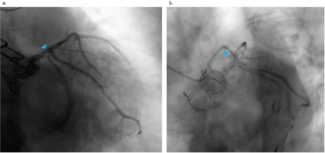

A 66-year-old male Jehovah’s Witness arrived at the emergency room having experienced typical persistent angina. Upon arrival, he was hemodynamically unstable.